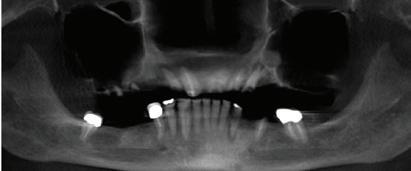

Dentures are a good replacement option for patients who are missing all of their teeth, but only if they fit well.

Impact on the bone by continuous hitting and pressure of a denture against the jaw every time you eat can make the bone underneath the denture go away. This causes the denture to become loose and slip. It may create the need for using paste or other means to hold the denture in place. Slipping dentures can make eating certain foods very difficult for patients. This happens most often with lower dentures.

Dental implants can be placed under the denture. Implants have offered the possibility of fully replacing teeth for over 30 years and are very safe and effective. When you make the denture stable by “snapping” it onto dental implants, you can provide a better level of comfort for the denture-wearer, and create new strength for eating the foods patients love.

Dental implants are very much like your natural teeth. They are quite easy to get used to, and they can reduce the amount of stress to the bone and jaw by helping provide an anchor for support. The implant acts as a natural root to help prevent additional bone deterioration and helps to deliver long lasting function.

Does Every Denture-Wearer Qualify?

This depends on the amount of bone loss that has already taken place. If the denture has been in place for many years and the ridge of bone under it is very thin, you may need to have a special scan done to decide if you are a candidate for the procedure. This scan will also look for any other defects that may be present to make sure you are healthy. Since implants are meant to last for a very long time, your health and wellness are important to the outcome.